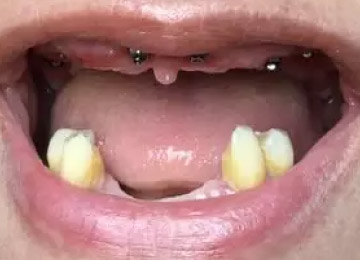

Имплантация зубов: фото «До» и «После»

Фото ДО

Фото ПОСЛЕ

Наведите для просмотра

All-on-4